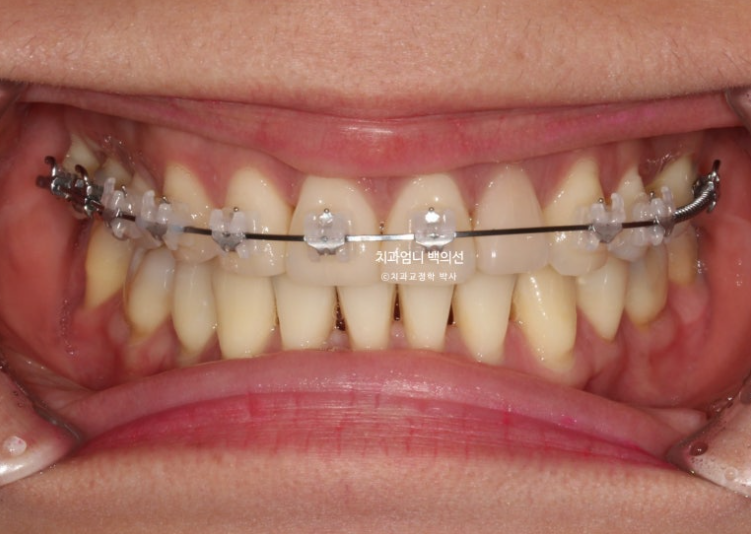

23년 8월 재교정치료를 위해 내원한 환자분입니다.

환자분은 어금니가 닿도록 끝까지 물면 아래턱이 뒤로 밀리는 증상때문에 재교정을 원했습니다.

또한 아래턱이 뒤로 밀리다보니 아래 앞니가 뒤로 너무 쑥 들어가보이는 부분도 개선을 원하셨습니다.

23.08

블랙트라이앵글과 중심선 불일치가 보입니다.

잇몸이 얇은편이라 작은어금니 부분에 잇몸퇴축도 보입니다.

얼굴에 비해서 위 앞니 중심선이 좌측으로 돌아간 상태인데

원인은 좌우 치아 갯수 차이에 있었습니다.

오래 전 했던 발치교정으로 작은어금니 4개가 없는 상태인데 좌측 첫번째 큰어금니 1개가 추가로 더 없습니다.

상악 좌측에만 치아갯수가 2개나 없는 것 입니다.